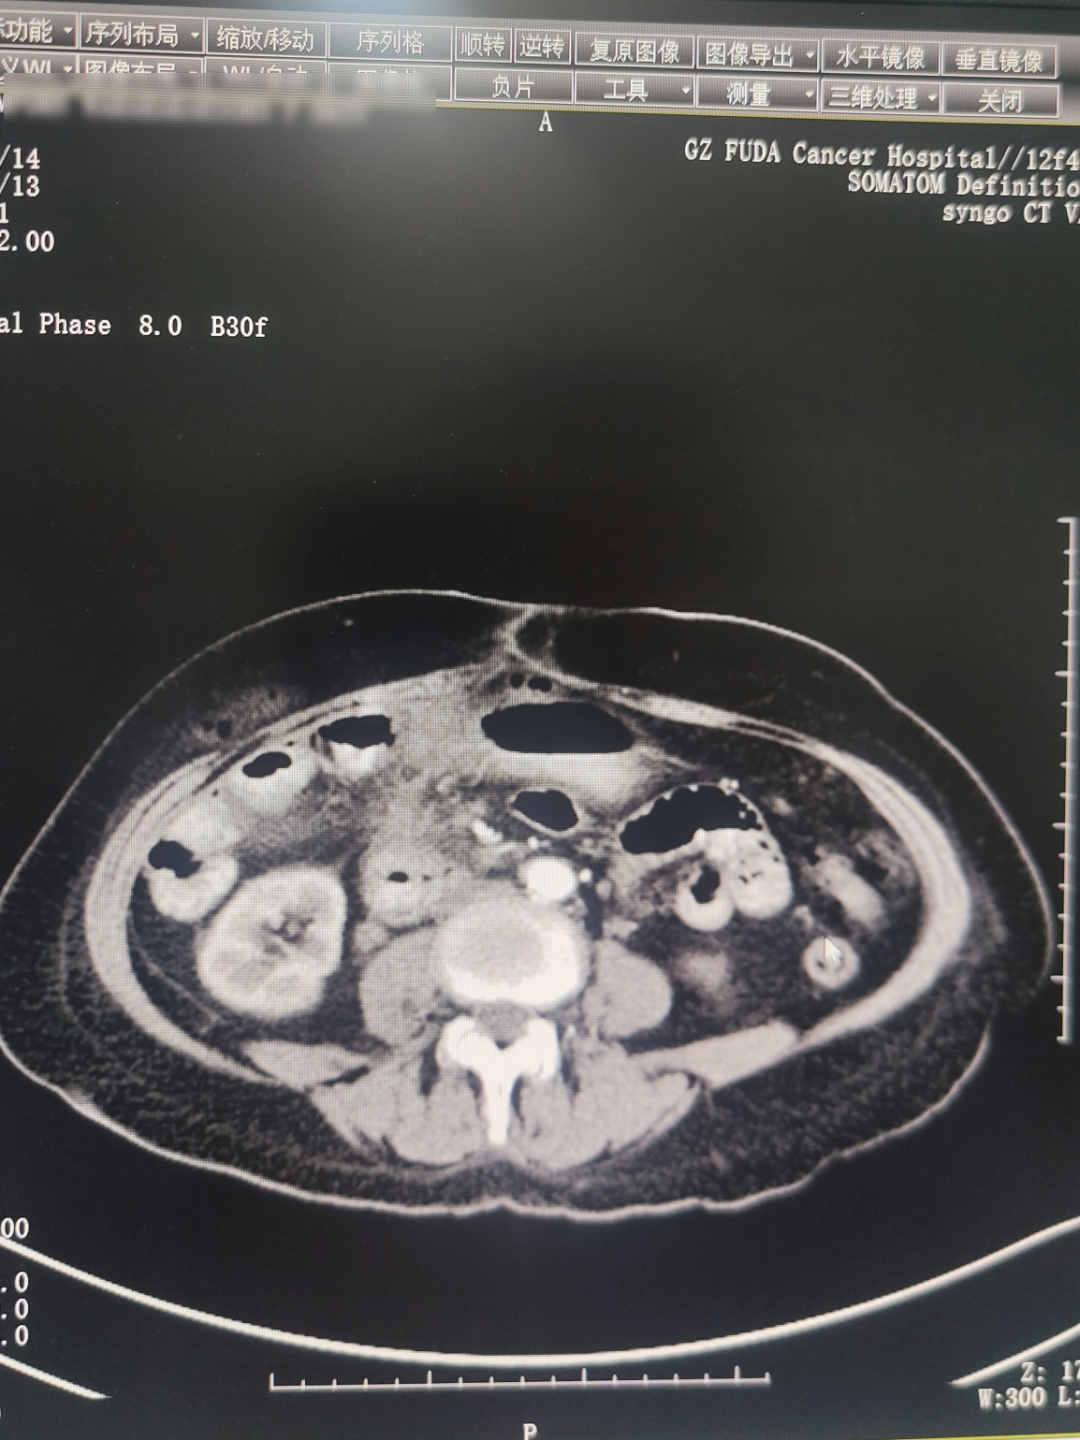

2025年5月影像